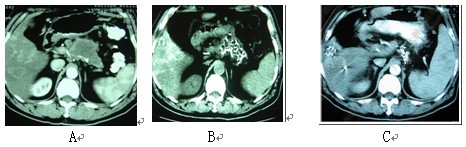

图2 男性,61岁。胰腺体尾部腺癌伴肝转移。A:治疗前;B:冷冻-碘粒子联合治疗后1个月复查;

C::治疗后6个月复查。血液CA19-9降至40IU以下。患者生存27个月。